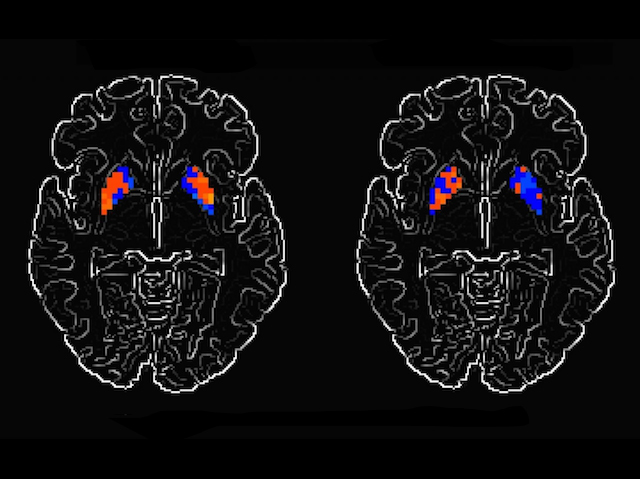

Parkinson’s disease progressively destroys certain cells in the brain, particularly those involved in movement, which is why patients tend to suffer from tremors, stiffness, and other mobility problems. Because assessing such physical symptoms can be subjective, researchers have been hunting for what’s known as a 'biomarker' of disease: a precisely measurable factor that accurately reflects disease progression. Now, by examining the brains of Parkinson’s patients, it seems they’ve found one. Scans of patients’ brains showed that activity in two brain regions – the putamen (coloured blobs) and the motor cortex – reduced as the disease worsened. The scan on the right, for example, was taken a year later than that on the left and shows a clear decrease in the red signal (activity). By monitoring this specific activity doctors should have a more definitive view of disease progression and, importantly, of whether any new drugs may be halting or reversing brain degeneration.